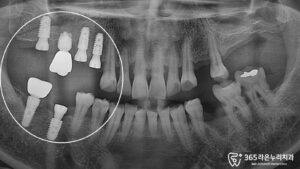

CT 정밀검사

임플란트 식립 전 정확한 치료 계획을 위해 CT 촬영을 실시했고 치아가 상실된 부위의 잇몸뼈 상태를 면밀히 분석했습니다.

오랫동안 치아가 없었던 부위는 잇몸뼈가 많이 흡수된 상태여서 임플란트만 단순히 식립하기에는 부족한 상황이었습니다.

따라서 임플란트 식립과 동시에 뼈이식술을 병행하여 장기적으로 안정적인 기반을 마련하는 것이 필요했습니다.